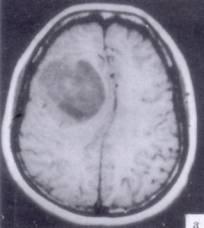

病历摘要:??患者男性,52岁。头痛伴呕吐2月,呕吐呈喷射性。既往身体健康。体检:神清,表情淡漠,反应迟钝,双眼底视神经乳头明显水肿,左鼻唇沟稍浅,左腹壁...

问题 病历摘要:??患者男性,52岁。头痛伴呕吐2月,呕吐呈喷射性。既往身体健康。体检:神清,表情淡漠,反应迟钝,双眼底视神经乳头明显水肿,左鼻唇沟稍浅,左腹壁反射减弱,左上下肢肌力4级,左Babinski征(-)。 术前的检查和治疗应包括下列哪些??提示:初步诊断考虑胶质瘤,拟手术治疗